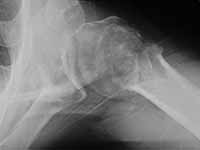

49 yo male RHD architect 3 mos s/p left prox humerus fx/dislocation in MCA presented today wanting know if he had any other treatment options at this time. He had initial PP, which was better reduced, but fell back into valgus impaction. He has 45 degrees FF, 40 degrees Abduction, 20 degrees ER of motion now w/ limited function.

Anyone consider ORIF and use Norian as reported for acute valgus impacted fx in Sept JBJS, Hemiarthroplasty or leave it alone?